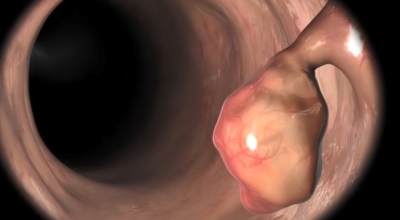

식도암은 다른암에 비교해 사망 가능성이 아주 높은 암이랍니다. 식도암 초기증상 발견 시에는 예후가 매우 좋지만, 2,3기에 발견될 시에는 사망하는 비율이 가파르게 오르게 되어요. 다만 초기에는 증상이 거의 없으므로 문제가 되어요. 초기에 관찰되는 경우는 내시경을 통한 방법말고는 거의 없다고 해요. 그러기에 주기적인 내시경은 필수겠죠.

안타깝지만 식도암 초기증상은 잘 느끼지 못해요. 하지만 방법은 있습니다. 그것은 바로 위 내시경 검사를 받는 것으로 보입니다. 위 내시경 검사를 받을 때 식도를 거쳐서 내시경 검사를 하므로 우리는 꼭 2년에 한번씩, 나이가 50대가 넘었다면 1년에 한번씩 내시경 검사를 받아야 해요.